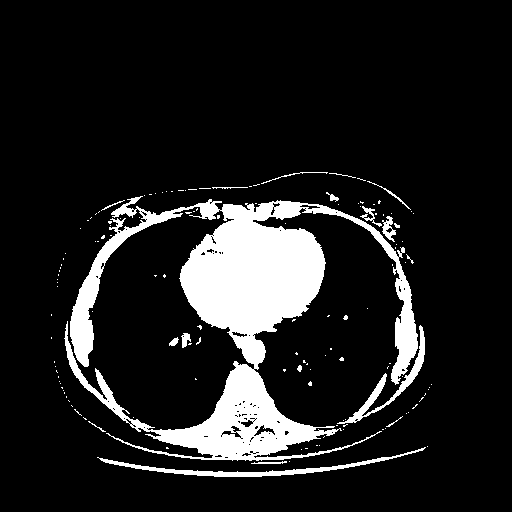

Original NATIVE CT scan (input)

Full window (WL 1023.5, WW 4095 β†’ Low βˆ’1024, High +3071)

Actual HU range: [-1024.0, 3071.0]